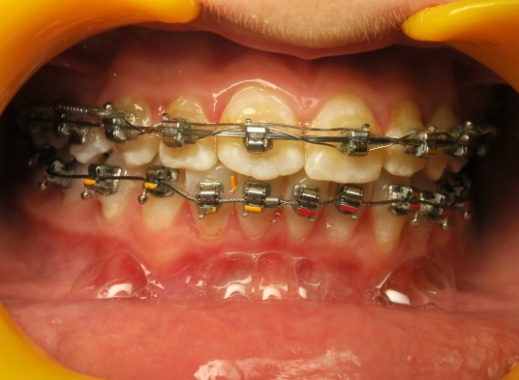

2 - Alignement par brackets autoligaturants

Le recul progressif des dents encombrées dans les espaces d’extraction créés à cet effet a été rendu possible grâce à l’utilisation de brackets autoligaturants, particulièrement efficaces pour respecter l’angulation et le torque des dents. Tous les espaces d’extraction ont été exploités pour résoudre l’encombrement, évitant ainsi tout recul des dents antérieures. L’occlusion obtenue est physiologique, en classe I canine et en classe II molaire thérapeutique.